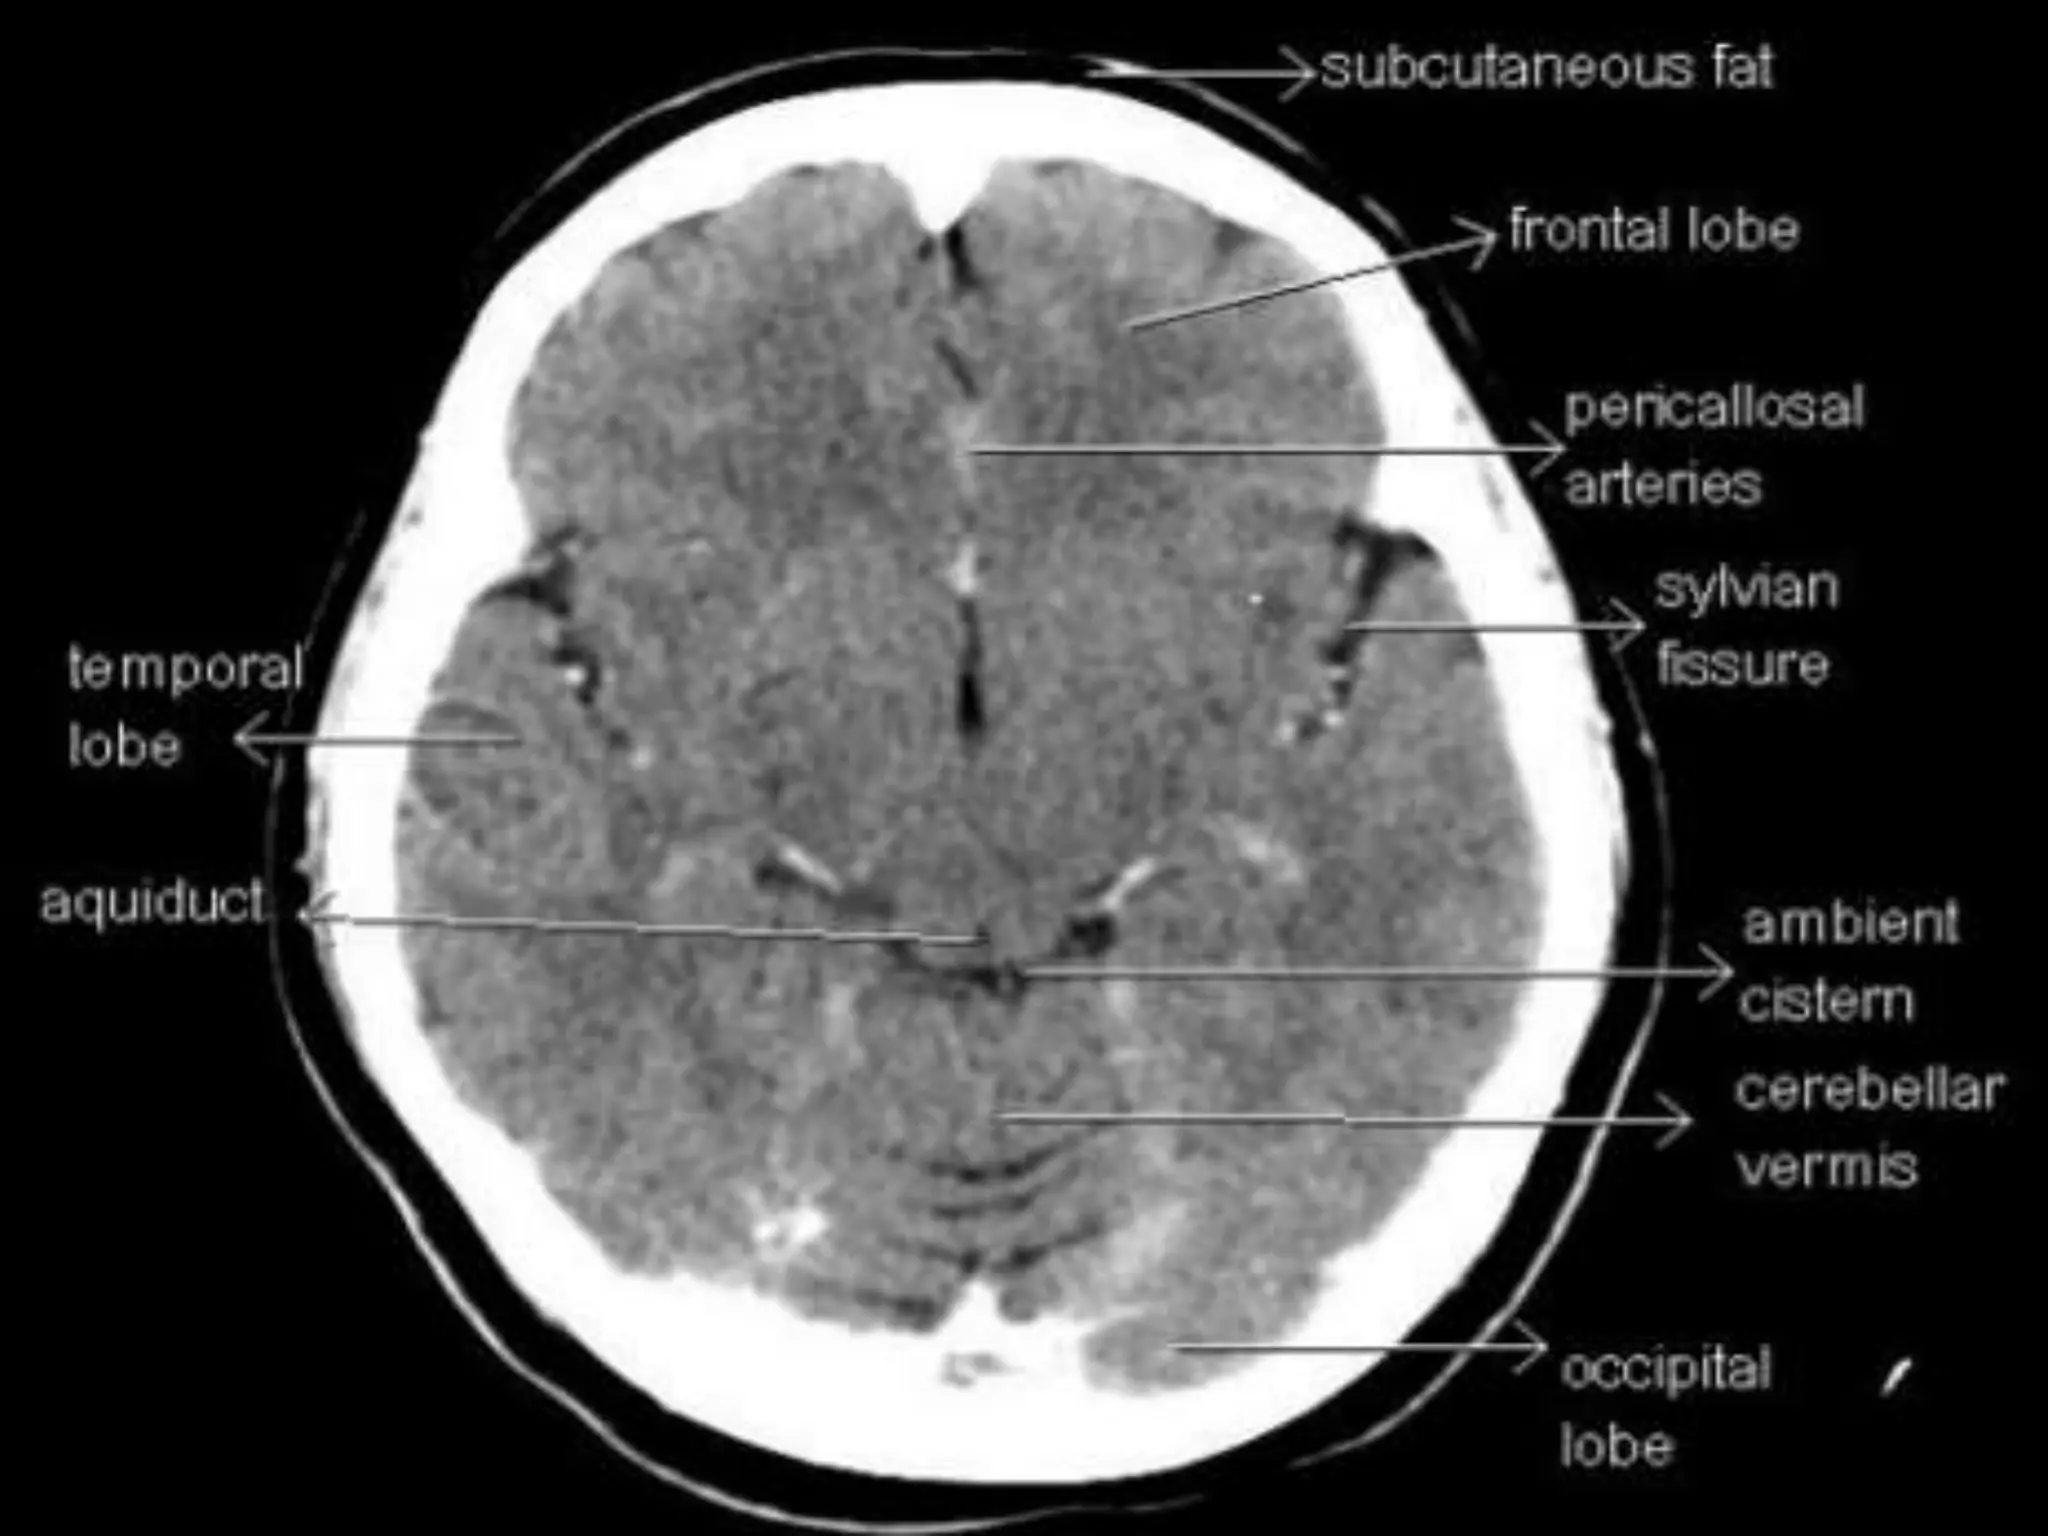

In the parietallobe, there are a postcentral gyrus, a superior parietal lobule, and an inferior parietal lobule. The postcentral gyrus is a primary somesthetic area involved in general body sensation. In the temporal lobe, the superior, middle, and inferior temporal gyri are separated by the two transverse sulci. The posterior fossa contains the cerebellum and brain stem. The posterior fossa is outlined by the clivus and petrous bones anteroinferiorly, the tentorium cerebelli superiorly, and the occipital bone posteroinferiorly. The cerebellum is located posteriorly in the two thirds of the posterior fossa, separated from the brain stem by the fourth ventricle. The brain stem occupies the anterior third of the posterior fossa, including the midbrain, pons, and medulla oblongata. The brain derives its vascular supply via two carotid and two vertebral arteries. The internal carotid artery bifurcates terminally into the anterior and middle cerebral arteries. The two vertebral arteries unite at the caudal border of the pons to form the basilar artery.

Sectional Anatomy: NormalAxial CT and MRI Anatomy. On CT and MR scans, the brain has been briefly viewed in infratentorial and supratentorial sections, as described below. CT scans are performed with a 15- to 20-degree angulation to the canthomeatal line at 8-mm increments. MRI scans are generally obtained parallel to the AC-PC line in the axial plane with 6-mm slice thickness. Using the sagittal view, the coronal sections are acquired parallel to the brain stem, and the sagittal sections are obtained perpendicular to the axial section. On MRI studies, cranial nerves IX and X can be demonstrated at this level because they emerge from the postolivary sulcus. The posterior aspect of the cerebellar hemispheres is outlined by the inferior portion of the cisterna magna.